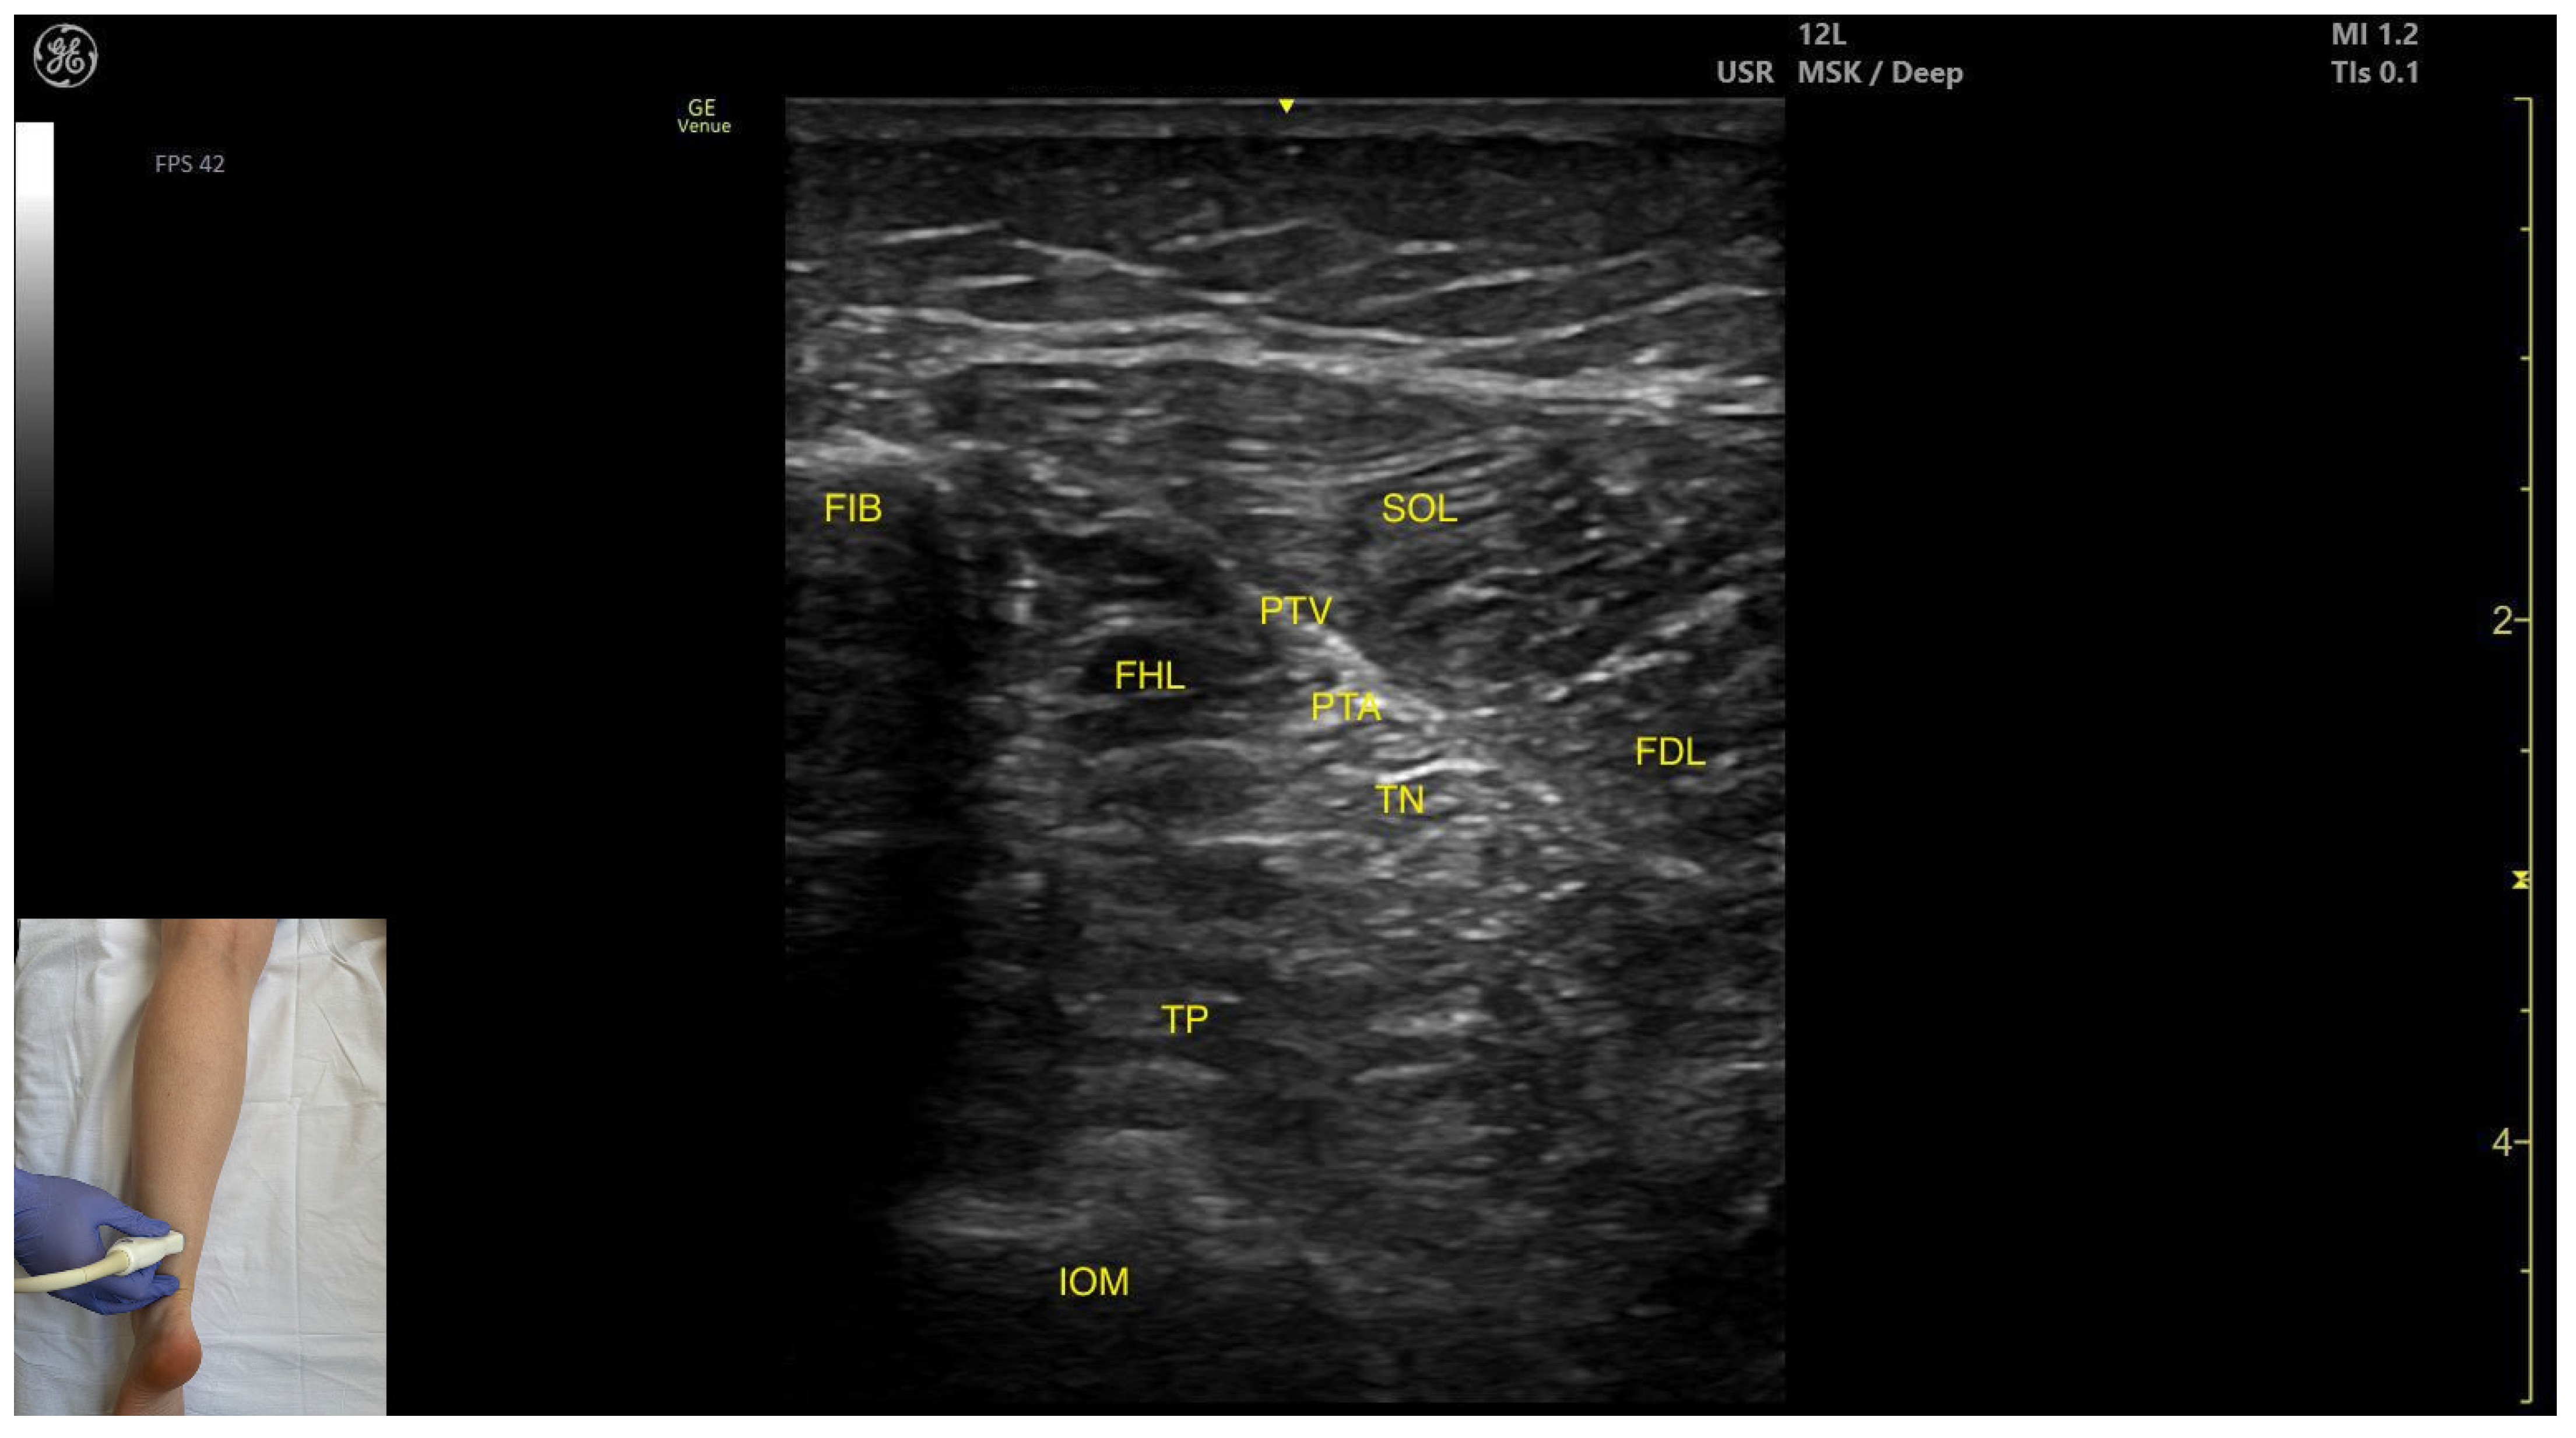

3.3.4. Posterior Window

Ultrasound Identification

Key Ultrasound Landmarks

- Muscle position: The tibialis posterior is the deepest muscle in the posterior compartment of the leg. It is bordered superficially and medially by the flexor digitorum longus, and superficially and laterally by the flexor hallucis longus. The interosseous membrane is located deep to the TP.

- Neurovascular bundle: In the intermuscular fascia between the TP and the FHL run the fibular artery and vein. Additionally, in the intermuscular fascia formed by the soleus, FDL and FHL are the tibial nerve, the posterior tibial artery and the posterior tibial vein.

- External fascia: The TP has pronounced fascia that separates it from the flexor digotorum longus and the flexor hallucis longus, which is relevant for BoNT-A injection.

- Dynamic evaluation: Muscle contraction is visible during ankle inversion and plantar flexion at the ankle joint.